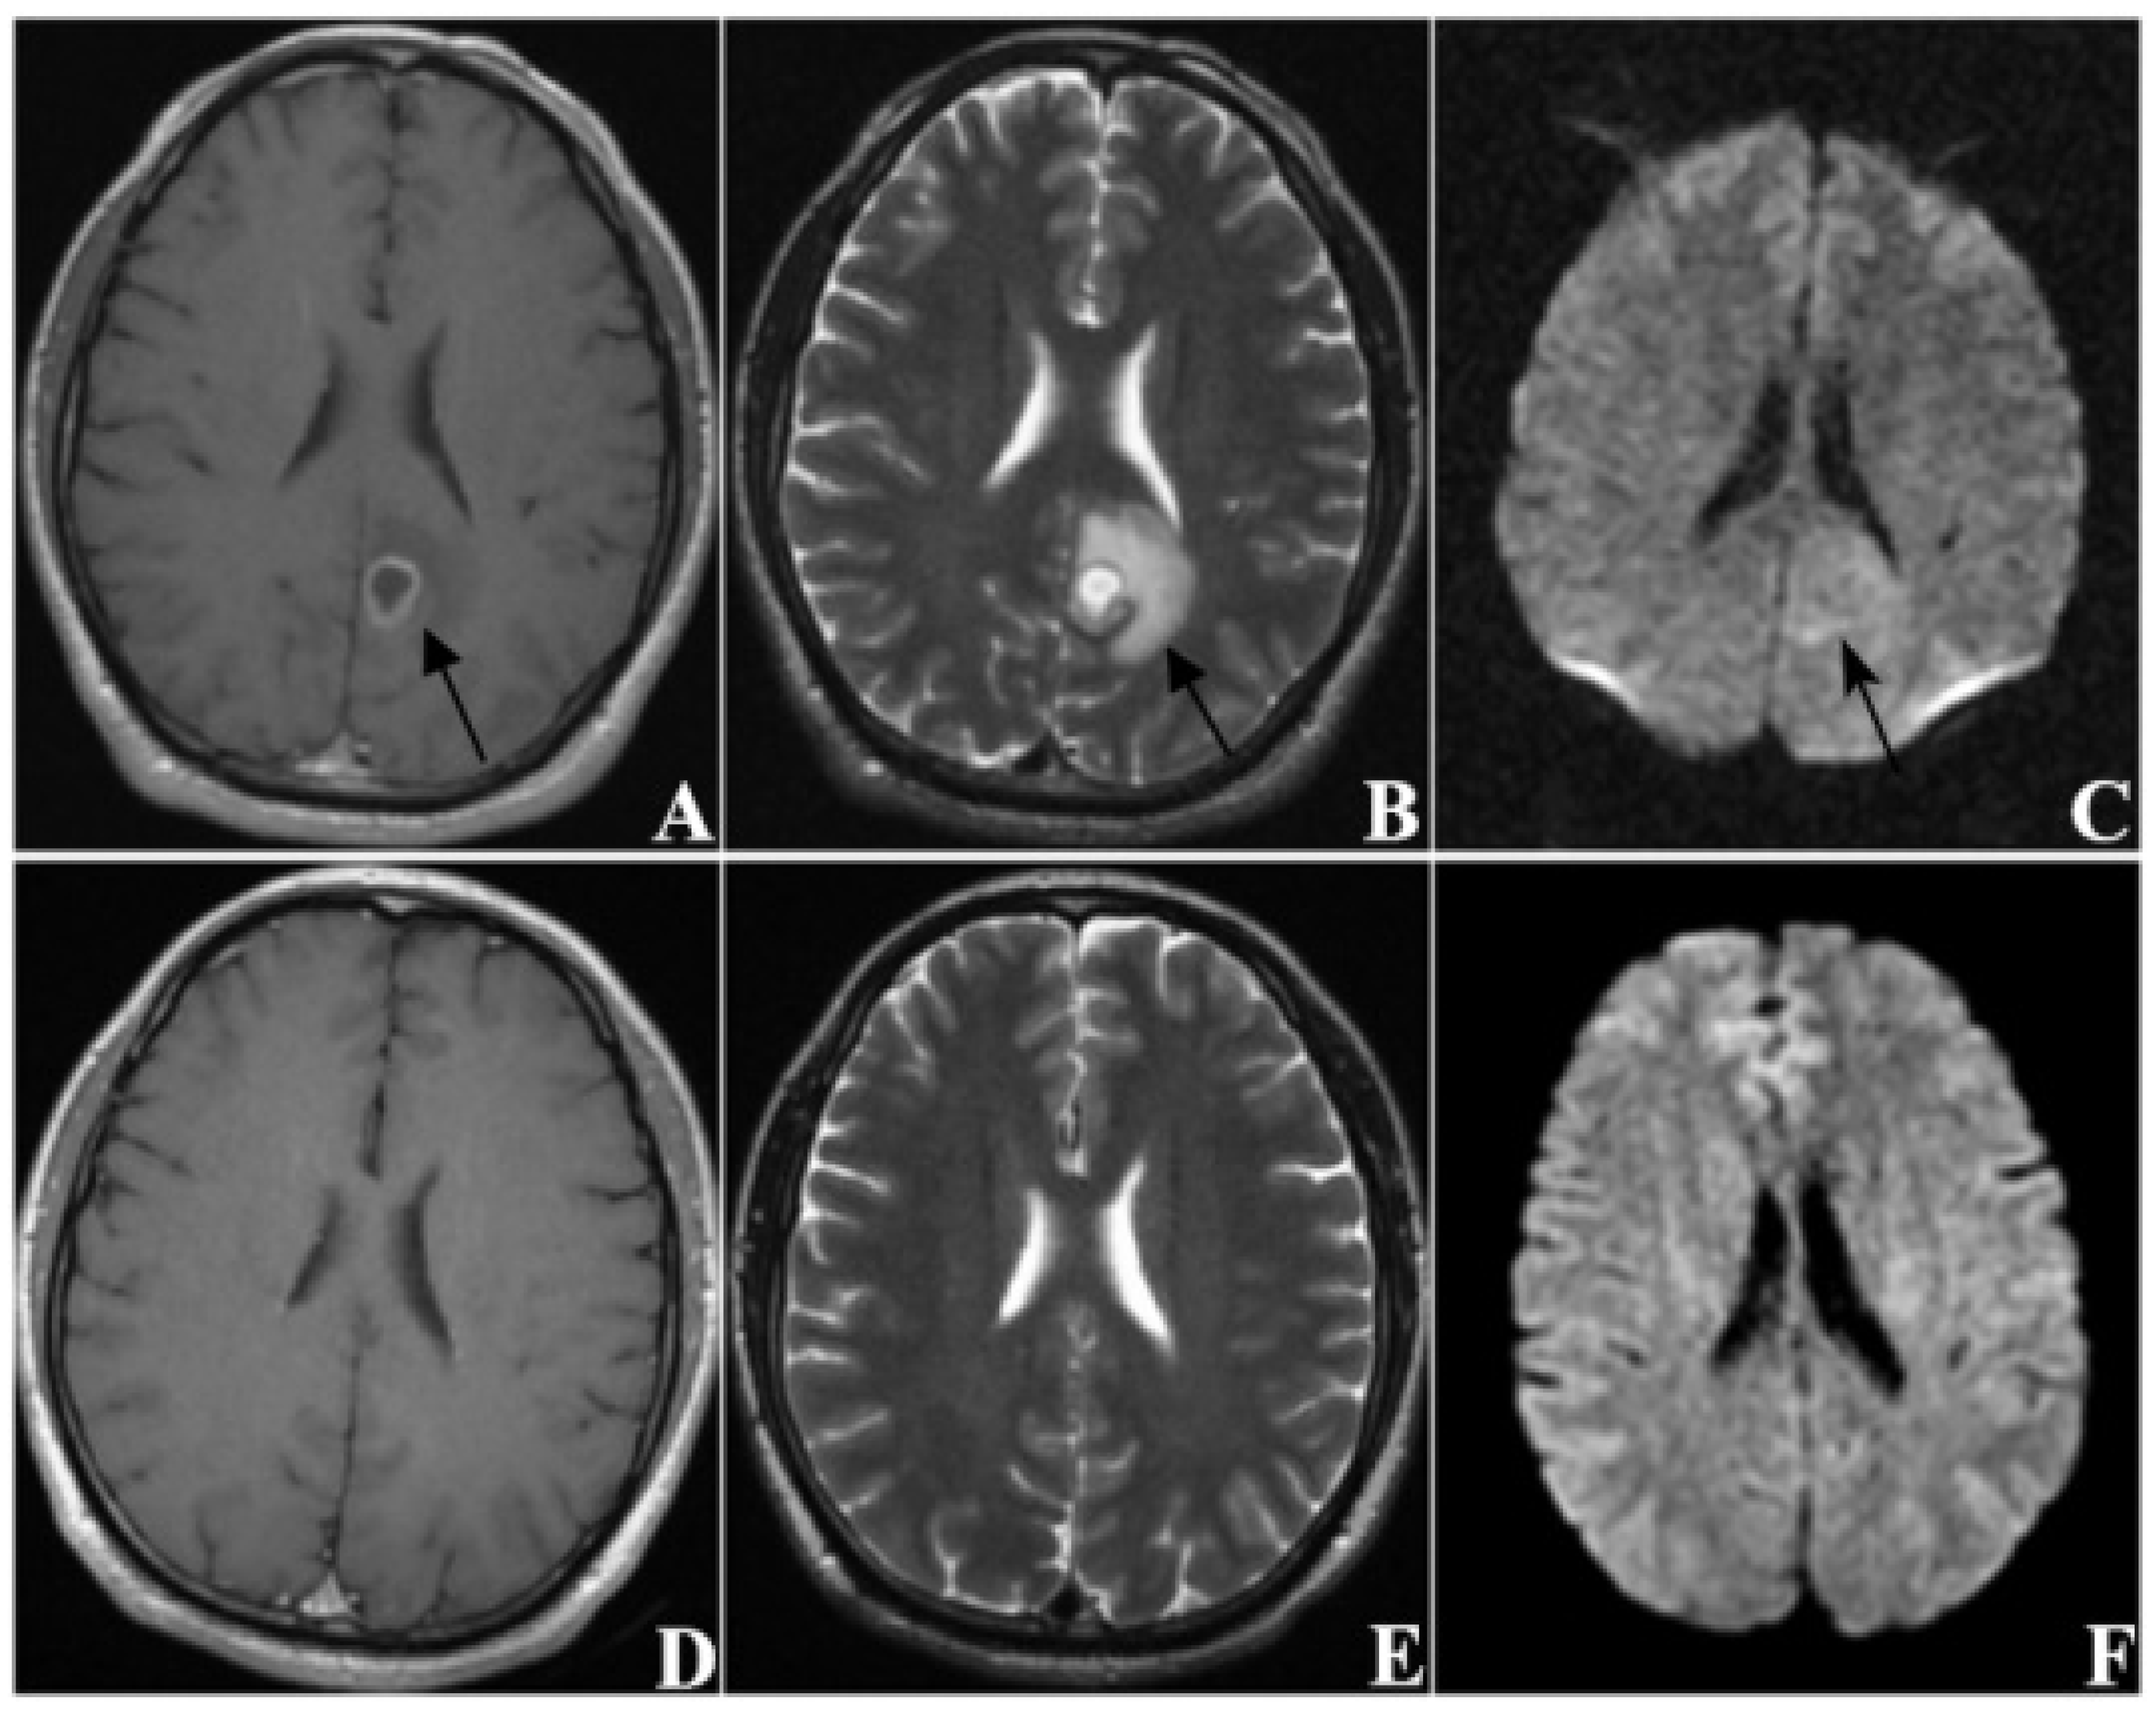

| DWI sequence signal | |

| hyper-intensity | 278 (86.1) |

| iso-intensity or hypo-intensity | 45 (13.9) |